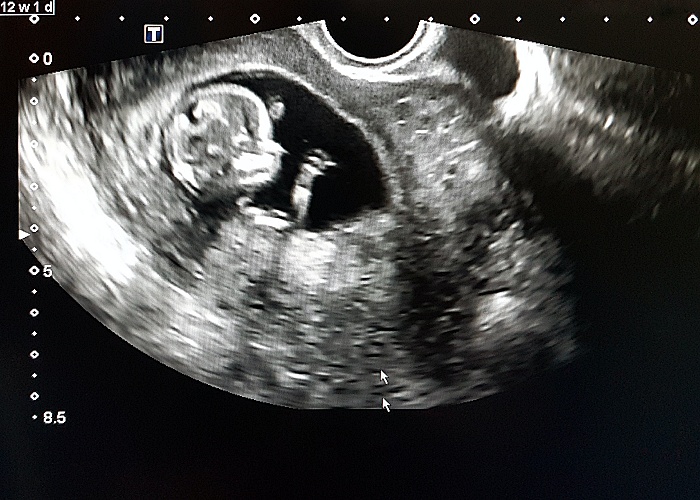

A routine prenatal ultrasound in the second trimester can identify early signs of Autism Spectrum Disorder (ASD), a study by Ben-Gurion University of the Negev and Soroka Medical Center found.

The researchers examined data from hundreds of prenatal ultrasound scans from the foetal anatomy survey conducted during mid-gestation. They found anomalies in the heart, kidneys, and head in 30% of foetuses who later developed ASD, a three-times higher rate than was found in typically developing foetuses from the general population. and twice as high as their typically developing siblings.

“Doctors can use these signs, discernible during a routine ultrasound, to evaluate the probability of the child being born with ASD,” said Menashe. “Previous studies showed that children born with congenital diseases, primarily those involving the heart and kidneys, had a higher chance of developing ASD. Our findings suggest that certain types of ASD that involve other organ anomalies, begin and can be detected, in utero.”

Multiple evidence support the prenatal predisposition of autism spectrum disorder (ASD). Nevertheless, robust data about abnormalities in foetuses later developing into children diagnosed with ASD are lacking. Prenatal ultrasound is an excellent tool to study abnormal fetal development as it frequently used to monitor foetal growth and identify foetal anomalies throughout pregnancy.